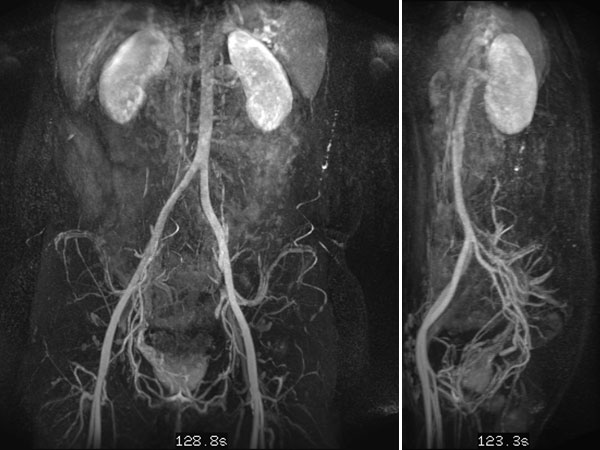

In dynamic contrast-enhanced MR angiography (late phase over 2 min after contrast administration, left coronal and right sagittal), the lesion shows no contrast enhancement or increased vascularization. It is practically invisible.

In the axial, fat-saturated T1-weighted images after contrast medium administration, an initially inhomogeneous accumulation of contrast medium in terms of contrast pooling occurs only slowly and incompletely. This is also relatively typical of a venous malformation.